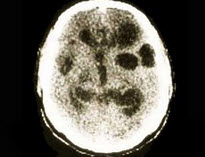

参考下图,猪囊尾蚴寄生于人脑部可引起脑囊尾蚴病。依据临床表现的不同,脑囊尾蚴病可以分为()

A.脑实质型

B.脑室型

C.软脑膜型

D.小脑型

E.脊髓型